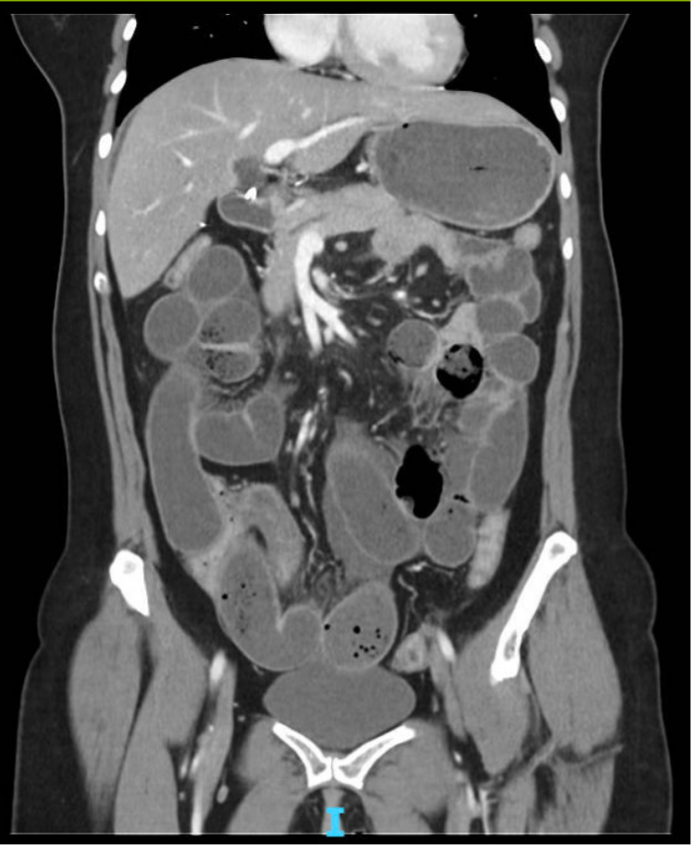

Small bowel obstruction with transition point in the pelvis at the level of wall-thickened distal ileum.

Diffuse wall thickening of the terminal ileum